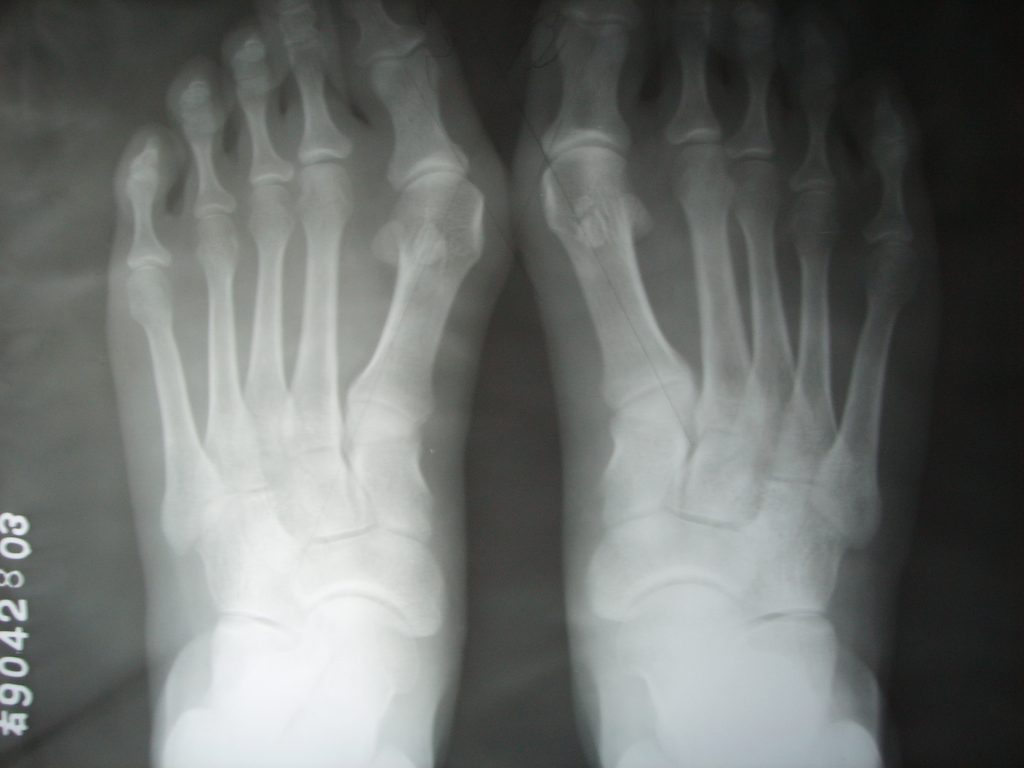

拇外翻X光情况

通过影像学检查我们可以看到,其实类似这样的拇外翻并没有典型的骨赘形成,所以轻度拇外翻也不是单纯的把第一跖骨头给磨掉就行。和典型的拇外翻一样,如果想要有效矫正拇外翻,还是得做第一跖列的截骨,需要把跖骨和(或)趾骨给截骨,以此来达成有效矫正拇外翻的效果。